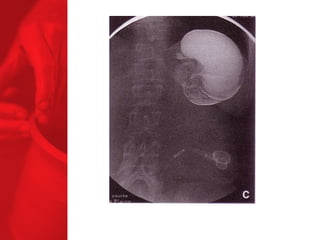

ANNEAU GASTRIQUE AJUSTABLEProcédure restrictive SAGB ® (anneau gastrique ajustable suédois) forme d'un sablier l'opération inverse peut être effectuée la digestion et l'absorption sont normales, aucun effets secondaires de la malabsorption moyenne de surcharge pondérale à 3, 4 et 5 ans après l'étude : 49, 55 et 57% respectivement* diminue le diabète de type 2 chez près de 77% des patients** *Laparoscopic SAGB: a 5-year Prospective Study, R. Steffen et al, Obesity Surgery, 13, 2003, 404-411 **Buchwald H, Avidor Y, Braunwald E, et al. Bariatric Surgery—A Systematic Review of the Literature and Meta-analysis. Journal of the American Medical Association 2004 Oct 13;292(14).

ANNEAU GASTRIQUE AJUSTABLE Procédure restrictive SAGB ®  (anneau gastrique ajustable suédois) forme d'un sablier l'opération inverse peut être effectuée la digestion et l'absorption sont normales, aucun effets secondaires de la malabsorption moyenne de surcharge pondérale à 3, 4 et 5 ans après l'étude :   49, 55 et 57% respectivement* diminue le diabète de type 2 chez près de 77% des patients** *Laparoscopic SAGB: a 5-year Prospective Study,  R. Steffen et al, Obesity Surgery, 13, 2003, 404-411 **Buchwald H, Avidor Y, Braunwald E, et al. Bariatric Surgery—A Systematic Review of the Literature and Meta-analysis. Journal of the American Medical Association 2004 Oct 13;292(14).